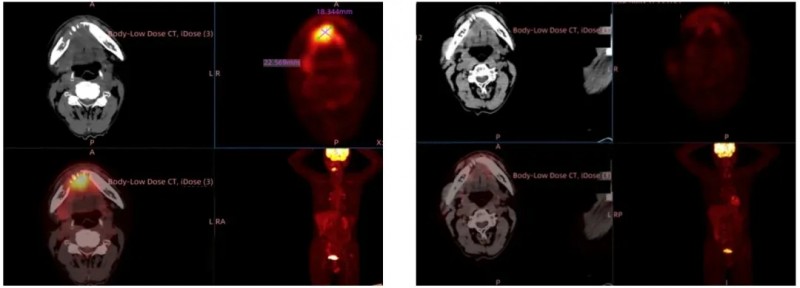

此前公布的典型案例显示,1例部分缓解(PR)患者的左侧锁骨上窝Virchow淋巴结(治疗前46.7mm),经GT201治疗4个月后缩小69%(详见下图)。

▲图源“ASCO”,版权归原作者所有,如无意中侵犯了知识产权,请联系我们删除